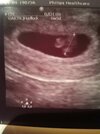

Wszystko póki co na miejscu. Dziś z usg 6+5 (z moich wyliczeń 6+6 ale dopuszczam ten jeden dzień obsuwy). Serduszko 141😍 trochę jej się nie spodobało ciałko żółte ale nie na tyle żeby się tym podobno przejmować. Pojawił się drobny krwiak pod kosmowka, ale podobno bezpiecznie ułożony i to on może być źródłem plamienia i jeszcze może wrócić trochę plamienie. Na tydzień L4 ze względu na krwiaka. Mam leżeć i odpoczywać